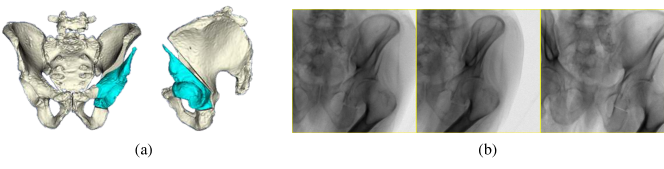

Developmental dysplasia of the hip (DDH) is a condition with lower than normal coverage of the femoral head. Patients with DDH frequently exhibit significant discomfort and are consequently less mobile. Severe arthritis is a common long-term consequence of untreated DDH, therefore surgical treatment is expected during the lifetime of a patient [1]. The periacetabular osteotomy (PAO) is a surgical procedure designed to preserve the natural joint of young patients with DDH[2]. In order to relocate the joint and increase femoral head coverage, the acetabulum must be freed from the remainder of the pelvis by performing osteotomies along the ilium, ischium, posterior column, and pubis. Many clinicians use intraoperative fluoroscopy to manually navigate osteotomes while performing the cuts. Even with fluoroscopic guidance, the ischial and posterior osteotomies introduce the risk of joint breakage due to their closeness to the acetabulum. Furthermore, the fluoroscopic views are difficult to mentally interpret and accurate determination of femoral head coverage remains a challenge after its relocation [3]. A simulated set of PAO osteotomies with fragment movement, along with corresponding simulated fluoroscopic images, are shown in Fig. 1.

Refer to caption

Figure 1: A simulated example of periacetabular osteotomies and a fragment reposition is shown in (a). The corresponding simulated fluoroscopic images are shown in (b).

Simulated data is derived from pre and postoperative CT scans of a cadaveric specimen (male, 88 years), for which a PAO was performed by an experienced clinician. Initial segmentations of the preoperative pelvis and femurs were obtained through an automated method [13], and refined manually. A rigid registration was performed to map the postoperative CT to the preoperative CT. Points along each of the osteotomies in the postoperative CT were manually digitized and transformed into the preoperative coordinate frame. Planes were fit to the transformed osteotomy points to obtain a baseline set of osteotomies. The segmentation of the acetabular fragment is determined by the set of pelvis labels contained within the convex hull defined by the cutting planes. Various fragment shapes were created by randomly rotating each cutting plane normal and translating by a random amount in the updated normal direction. Collision detection against other bones was conducted to ensure randomly sampled movements of the fragment and femur were valid. Soft-tissue is incorporated into the fluoroscopic image simulation by warping fragment and femur voxels within the volume and overwriting any overlapping soft-tissue voxels. Random intensities in the HU range of muscle are used to fill any “holes” left by relocating the acetabulum and femur. Fluoroscopic images were simulated similar to the procedure described in [14]. Fig. 1 shows a relocated simulated fragment, and the corresponding set of 2D fluoroscopic images.